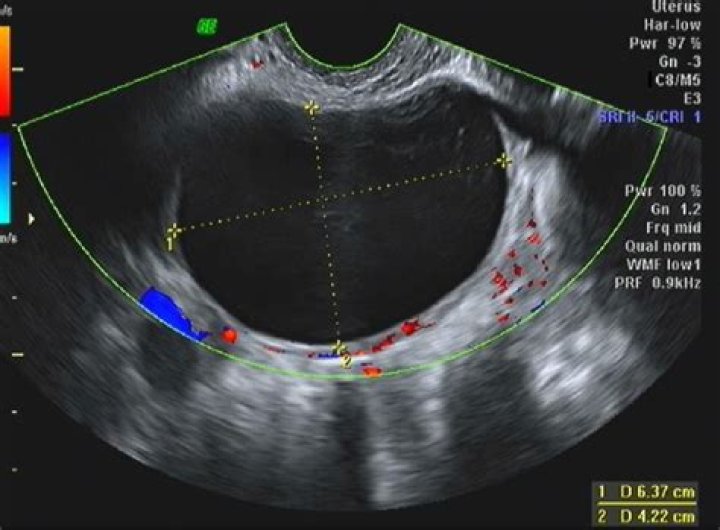

A simple cyst is a round or oval anechoic fluid collection with smooth thin walls, no solid component or septation, and no internal flow by using color Doppler imaging (Fig 1). When describing cysts in the pelvis, we use the term adnexal if the cyst is not clearly arising from the ovary.

What is considered a large adnexal mass?

Is an adnexal mass a cyst?